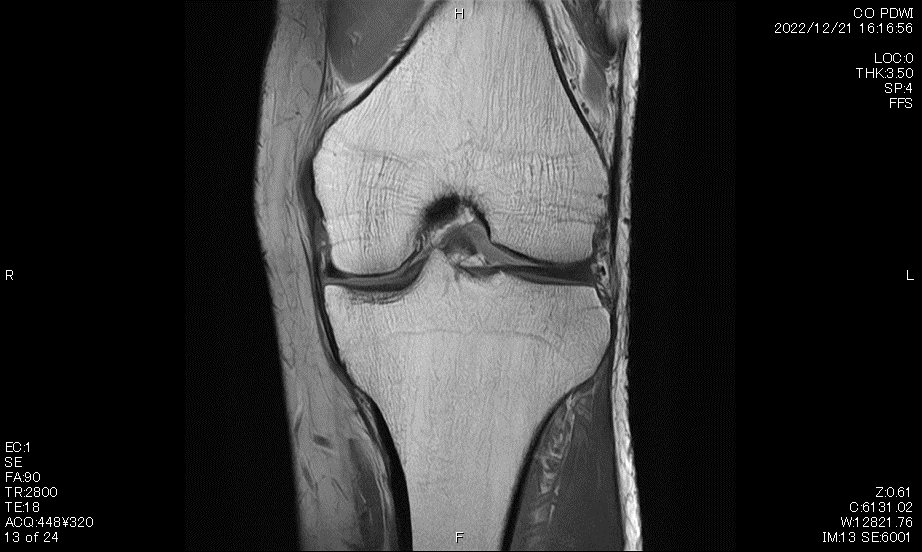

MRI検査

MRI (磁気共鳴画像) 装置は、強い磁場を形成する装置で人体に特殊な電磁波を当てて撮影を行っています。また、放射線による被ばくはありません。

当院では、Canon製 Vantage Galan 3.0TとCanon製Vantage Titan 1.5T の2台で検査を行っています。磁場強度の違いや、静音設計、開口径の大きさなどの特徴があり、検査内容に合わせて医師の判断で装置を使い分け、精度の高い良好な画像を提供しています。

主に頭部、骨、軟部組織の検査を始め、肝臓ダイナミックなど幅広く検査を行っています。